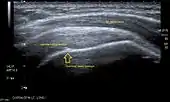

Ultrasound

There are several advantages of ultrasound. It is relatively cheap, does not emit any radiation, is accessible, is capable of visualizing tissue function in real time, and allows the performance of provocative maneuvers in order to replicate the patient’s pain.[26] Those benefits have helped ultrasound become a common initial choice for assessing tendons and soft tissues. Limitations include, for example, the high degree of operator dependence and the inability to define pathologies in bones. One also has to have an extensive anatomical knowledge of the examined region and keep an open mind to normal variations and artifacts created during the scan.[27]

Although musculoskeletal ultrasound training, like medical training in general, is a lifelong process, Kissin et al. suggests that rheumatologists who taught themselves how to manipulate ultrasound can use it just as well as international musculo-skeletal ultrasound experts to diagnose common rheumatic conditions.[28]

After the introduction of high-frequency transducers in the mid-1980s, ultrasound has become a conventional tool for taking accurate and precise images of the shoulder to support diagnosis.[29][30][31][32][33]

Adequate for the examination are high-resolution, high-frequency transducers with a transmission frequency of 5, 7.5, and 10 MHz. To improve the focus on structures close to the skin an additional "water start-up length" is advisable. During the examination the patient is asked to be seated, the affected arm is then adducted and the elbow is bent to 90 degrees. Slow and cautious passive lateral and/or medial rotations have the effect of being able to visualize different sections of the shoulder. In order to also demonstrate those parts which are hidden under the acromion in the neutral position, a maximum medial rotation with hyperextension behind the back is required.[34]

To avoid the different tendon echogenicities caused by different instrument settings, Middleton compared the tendon’s echogenicity with that of the deltoid muscle, which is still lege artis.[35][36]

Usually the echogenicity compared to the deltoid muscle is homogeneous intensified without dorsal echo extinction. Variability with reduced or intensified[37] echo has also been found in healthy tendons. Bilateral comparison is very helpful when distinguishing and setting boundaries between physiological variants and a possible pathological finding. Degenerative changes at the rotator cuff often are found on both sides of the body.[38] Consequently, unilateral differences rather point to a pathological source and bilateral changes rather to a physiological variation.[36]

In addition, a dynamic examination can help to differentiate between an ultrasound artifact and a real pathology.[39]

To accurately evaluate the echogenicity of an ultrasound, one has to take into account the physical laws of reflection, absorption and dispersion. It is at all times important to acknowledge that the structures in the joint of the shoulder are not aligned in the transversal, coronal or sagittal plane, and that therefore during imaging of the shoulder the transducer head has to be held perpendicularly or parallel to the structures of interest. Otherwise the appearing echogenicity may not be evaluated.[40]

![]() Longitudinal ultra sonography of the supraspinatus tendon |

![]() Transversal ultra sonography of the supraspinatus tendon |